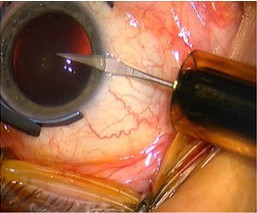

4、超声碎天然晶体

秒激光是目前已被证实拥有最短脉冲的激光类别,它最快能在千万亿分之一秒内释放超短脉冲能量,因此非常实用于需要高精确度的眼科手术。在这之前,该技术主要用于激光矫正视力手术。

将飞秒激光应用于白内障手术是医生们非常关心的话题。飞秒激光辅助白内障超声乳化手术,是利用飞秒激光代替医生划开切口,并预先分割患者眼睛囊膜内的浑浊晶体,整个过程都有电脑扫描成像技术辅助,医生再用超声波去除晶体。该手术的伤口复原时间虽与超声乳化手术相同,但患者更快恢复视力。